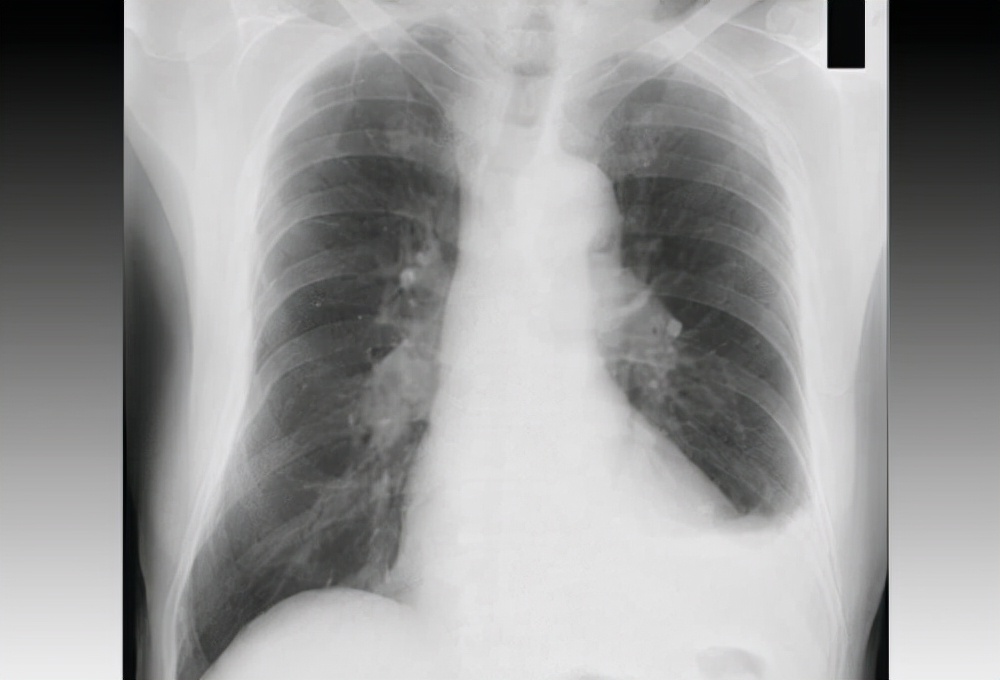

到了医院,给他做了CT,抽血检查、包括尿检。

医生看了检测报告后也是感到非常的诧异,因为他身体的各项指标都没有问题,因为一个普通人长期食用沙子的话,会对自己的肠胃造成不可逆的伤害,

这个小伙天天食用,身体的各个器官竟然都是非常的健康,片子里显示他肠胃的部分,虽然有部分残留的沙子,但也无伤大雅,这让医生很是不解,直呼神人!